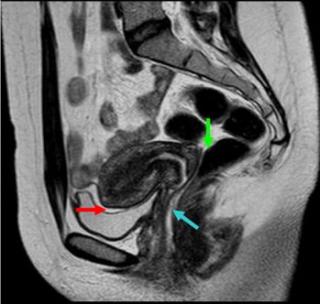

Магнитно-резонансная томография при эндометриозе позволяет точно определить степень продвижения и площадь поражения.

Что видно в результатах

Результаты представлены на диске или другом носителе. Специалист выдает заключение, в котором отмечает локализацию эндометриоза, степень развития, глубину инфильтрации и возможные осложнения. Окончательный диагноз ставит гинеколог.

Результаты МРТ показывают:

- утолщение стенок матки;

- эндометрий в яичниках, маточных трубах;

- небольшие кисты в соединительной или мышечной ткани;

- неоднородность структуры тканей;

- спайки и узелки.

Яркие пятна при эндометриозе